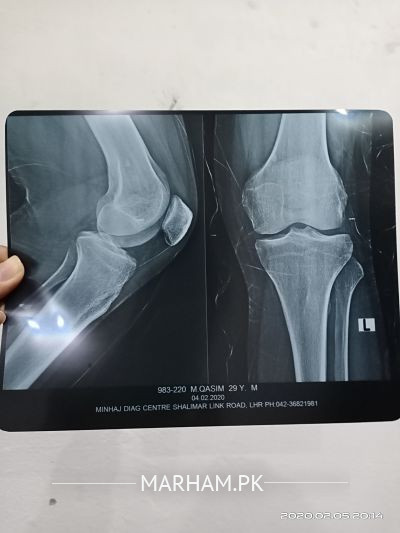

i was feeling a cracking sound in my left knee joint . can dr plz see my xray attached and tell me if anything looks wrong

No apparently abnormal

X-ray is apparently normal and cracking sound are cause by multiple reasons need to be examine.

X-ray k sth sth apky knee ka examination b zaruri Hy..

kisi achy Orthopedic Surgeon ko check krwa lijye..